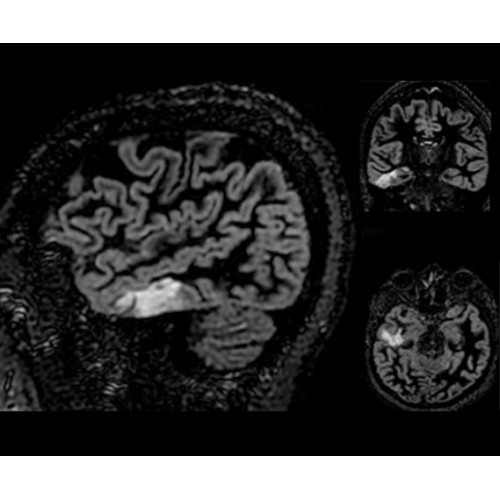

SIGNA PET/MR 3.0T — это гибридная система, в которой совмещаются две принципиально разные технологии — магнитно-резонансную томографию (МРТ) и позитронно-эмиссионную томографию (ПЭТ). Система отличающийся высокой чувствительностью и эффективностью и предназначена для диагностики в области онкологии, неврологии, кардио-васкулярных исследований, исследований воспалительных процессов.

Компания GE Healthcare представляет революционную, полностью интегрированную систему SIGNA PET/MR1, в которой сочетаются времяпролетная технология (TOF) и возможности напряженности магнитного поля 3.0 Тл. Мы поможем вам поднять исследования на более высокий уровень. SIGNA PET/MR позволяет достичь впечатляющей точности и скорости исследований, а благодаря новейшей технологии реконструкции Q.Clear2 качество изображений улучшается в два раза. Кроме того, в систему включен полный набор клинических приложений и гибких катушек для проведения любых видов исследования, открывая для вас возможности визуализации, о которых вы даже не догадывались.

Кроме того, в результате использования технологии TOF и инновационной технологии реконструкции Q.Clear вы сможете добиться прекрасного соотношения сигнал/шум. А благодаря технологии нулевого времени эхо (ZTE) визуализировать костную структуру без ионизирующего излучения. Все эти разработки для улучшения качества сканирования и точности анализа помогут вам использовать весь потенциал ПЭТ/МРТ.

• Специальный пакет приложений для измерения и сравнения объемных изображений ЦНС с нормами поможет вам в диагностике нейродегенеративных заболеваний, а дополнительные инструменты визуализации — в постановке точного диагноза с помощью бета-амилоидов и радиоизотопных маркеров ФДГ.